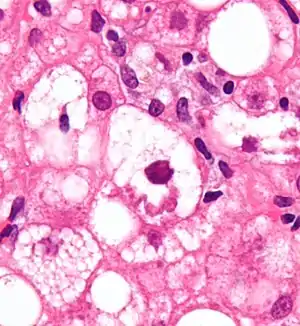

Mallory bodies are highly eosinophilic and thus appear pink on H&E stain. The bodies themselves are made up of intermediate cytokeratin 8/18 filament proteins that have been ubiquitinated, or bound by other proteins such as heat shock proteins, or p62/Sequestosome 1.[5]

Liver micrograph showing abundant Mallory bodies, as seen in alcohol use disorder.